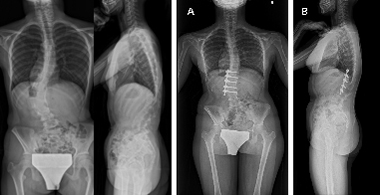

後方矯正固定術

せなかを切開してチタンなどで作られた椎弓根スクリューをせぼねに挿入して、ロッドと呼ばれる金属のバーで固定して、せぼねの矯正と固定を行います。術後に手術部の安静を保つために装具を3-6ヶ月程度着用します。

せなかを切開する場合が多いですが、状態によっては側方経路腰椎椎体間固定術(Lateral Lumbar Interbody Fusion: LLIF)や、経皮的椎弓根スクリュー(Percutaneous Pedicle Screw: PPS)をはじめとした体への負担を軽減する手法も取り入れられています。